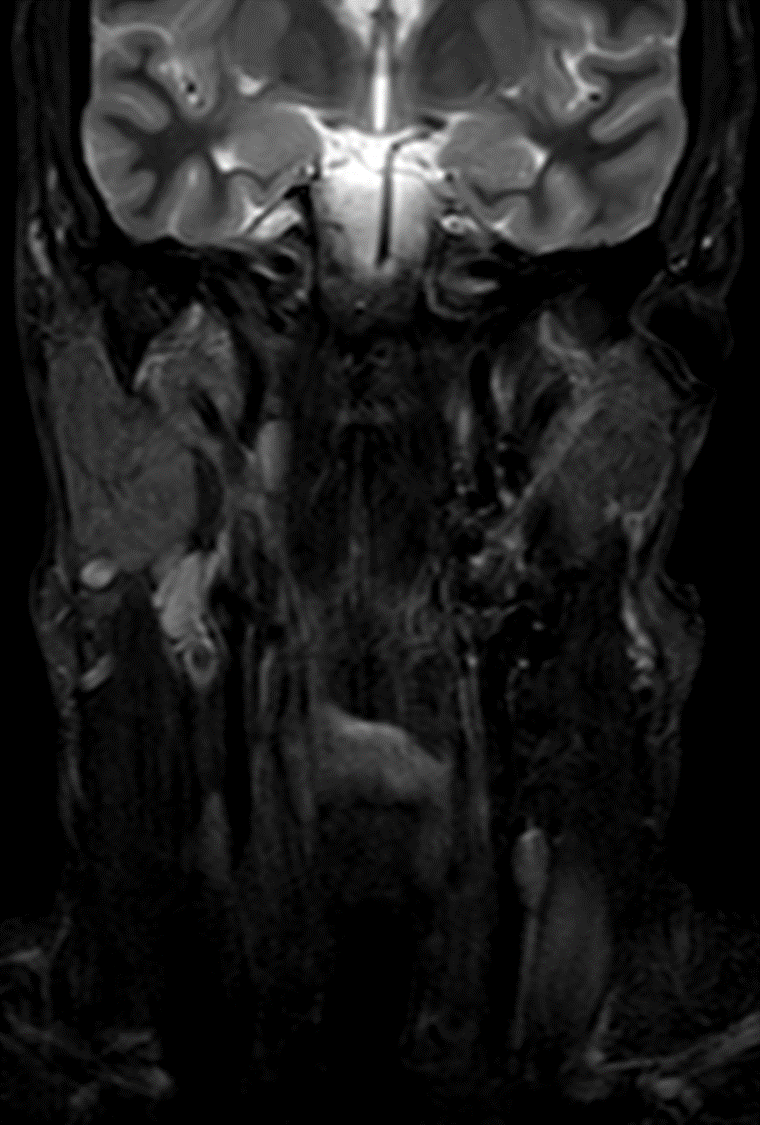

Clinical Pearl; Left Car...